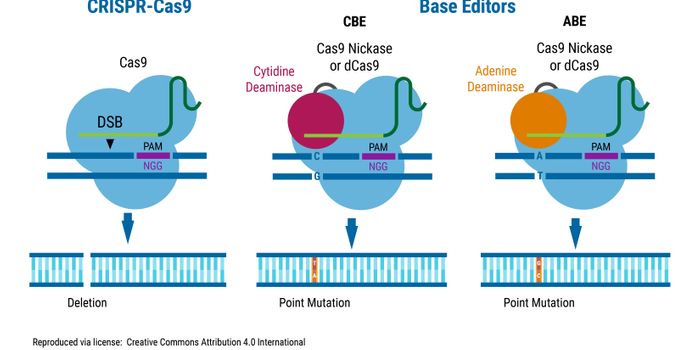

APR 25, 2024Cell & Molecular BiologyThe human genome is contained within the nucleus of cells. The genome is well protected, but many things can cause DNA d ...

APR 19, 2024Genetics & GenomicsThere are some genes that can promote cancer; they are sometimes called oncogenes, and in tumor cells, mutations are oft ...

MAR 08, 2023CancerGenetic modification of mammalian cells has vast use in biotherapeutics development and basic research applications. An ...

OCT 13, 2022CancerPoint mutations change one or very few nucleotides in DNA, but they cause an estimated 30,000 genetic diseases in humans ...